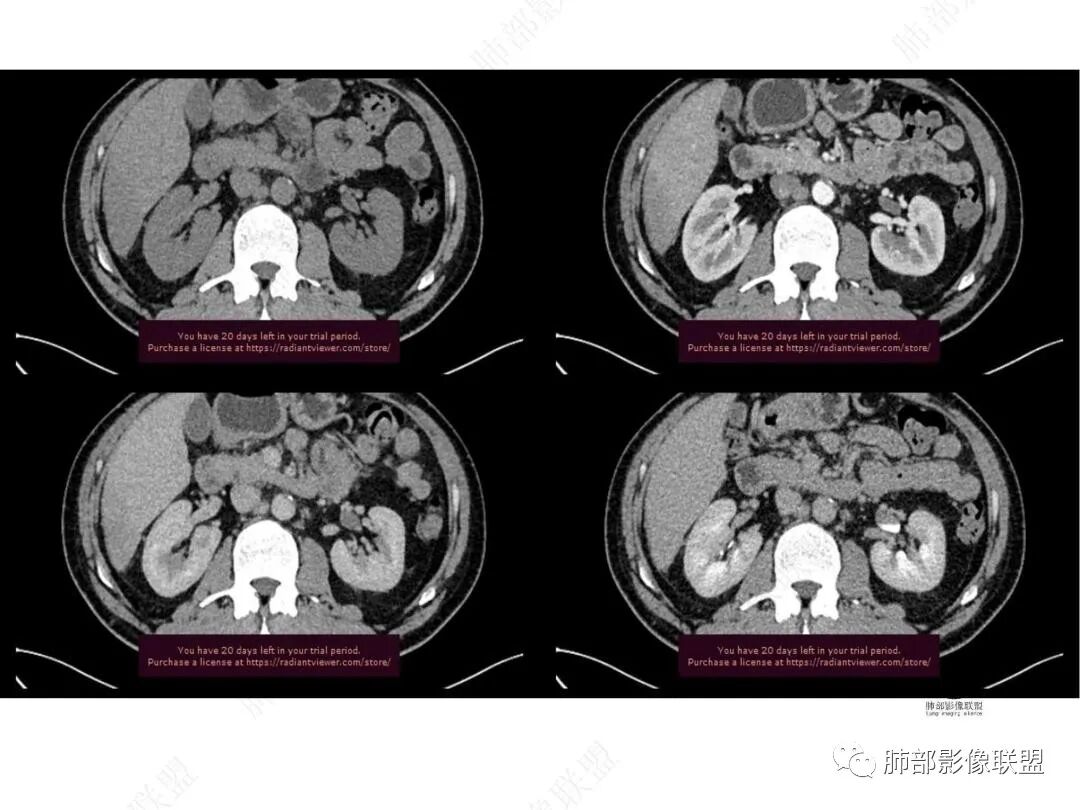

平扫图像

增强图像

CT值信息

男,49,低热3月。胸部CT:右肺上叶前段纵隔旁见团片影,部分边缘毛糙,部分平直、内收,邻近卫星灶、晕征,重建L征?支气管管壁增厚、进入后堵塞;纵隔可见肿大淋巴结;病灶密度较均匀,中度强化。肝脏片状低密度影,边缘模糊。考虑炎性病变,PC?TB?鉴别腺癌。

中年男性,反复低热3月伴近期乏力及右上腹隐痛,白细胞,中性粒及淀粉样蛋白A增高,PCT不高,IGA、IGg增高,类风湿因子增高,未提供IGg4水平,影像改变,左侧肋骨陈旧性骨折(2020年已存在)右上叶前段胸骨旁的胸膜下新发病灶,支气管进入后一段才堵塞,肺动脉进入,走行自然,未见破坏,明显均匀强化,气管及支气管壁有增厚,钙化,纵隔内淋巴结增大,均匀强化,无坏死,纵隔内脂肪混浊,局部强化,肝内低密度灶,延迟强化(肺内病灶,淋巴结、混浊脂肪,肝内病灶强化均一致,且均为延迟强化)。初步考虑:免疫相关性炎症,IGg4相关炎症可能大,依据:IGA、IGg增高(未提供IGg4,可能是故意隐藏了),类风湿因子增高,炎性指标增高,但PCT不高,细菌感染可能就变小,加上病变同时累及肺、纵隔淋巴结,纵隔内脂肪、肝。

1.中年男性,临床发热,症状较轻,中长病程,炎性指标轻度增高。

2.右肺上叶纵隔旁新发实性密度病灶,密度均匀,轻度强化,未见空洞、液化坏死及钙化,血管穿行自如,支气管进入后狭窄截止。灶周磨玻璃影边界不清,病灶未见明显分叶毛刺,平直、轻度收缩、周围偶见结节影,但未见树芽征。注意纵隔胸膜侵入或突入比较明确。纵隔淋巴结轻度增大。

4.肝脏病灶没有假包膜,没有动脉早期强化,没有肝硬化,未见扩张胆管,未见环形强化,也未显示靶征,缺乏肝细胞肝癌、胆管细胞癌、转移癌或肝脓肿特征。